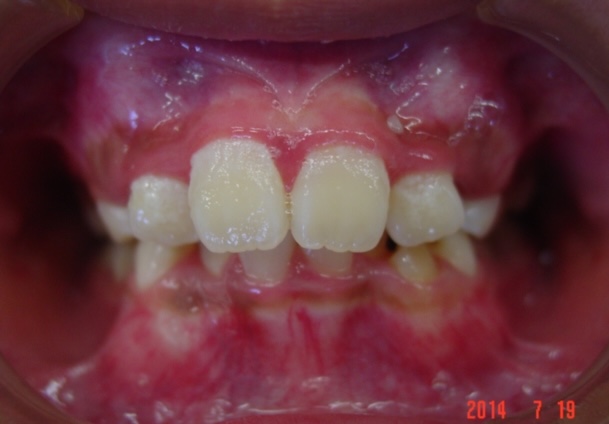

症例1-③

そこで当院では、ここからは、当院の成人非抜歯の技術を用いて、永久歯を抜くことなく(親知らずは除く)治療をゴールまでもって行きます。

症例1-③の写真が完成時の所見です。いかがでしょう、口もとも美しくきれいな永久歯列の完成です。